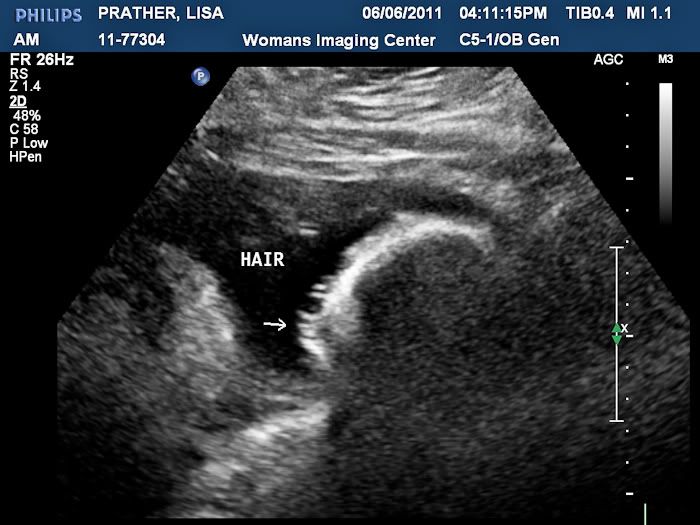

Symptoms: Heartburn, heartburn, heartburn- it has gotten really bad! They say that if you have bad heartburn, the baby has lots of hair. At our ultrasound yesterday, the technician said he has lots of hair, so I guess it's true!

The ultrasound technician said he had lots of hair. No wonder I've been having such bad heartburn.